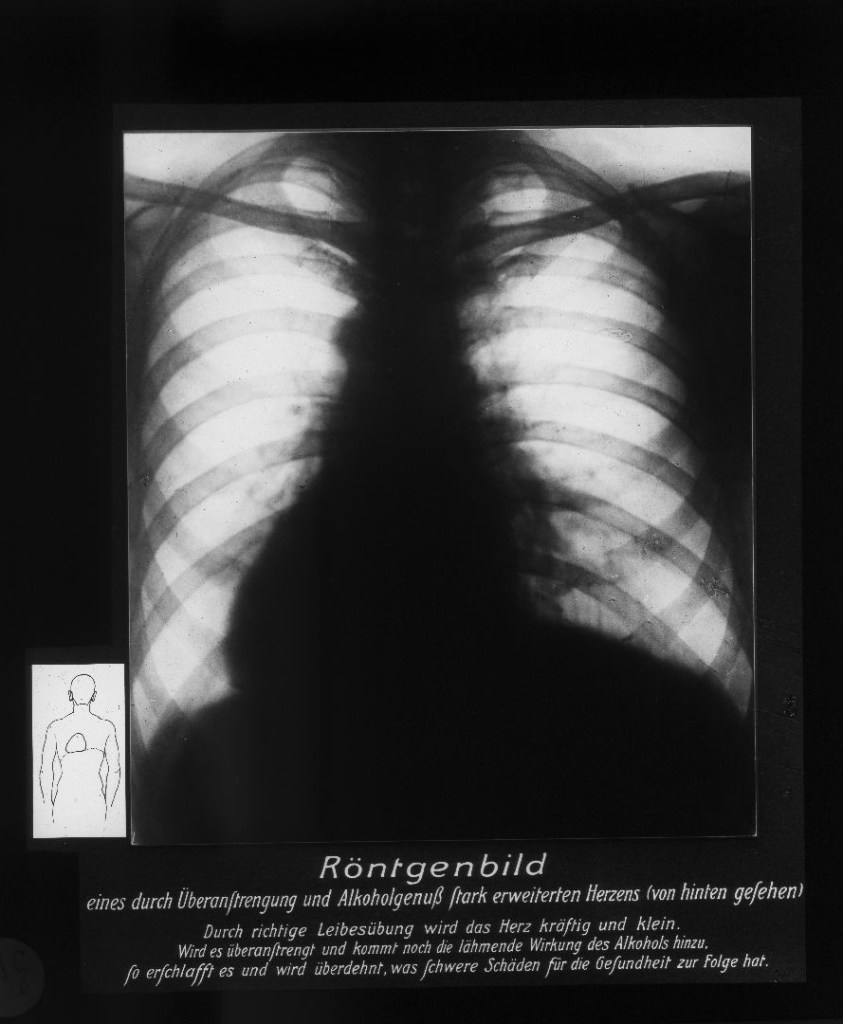

Auch mikroskopische Darstellungen wurden gezielt eingesetzt, um naturwissenschaftliche Erkenntnisse und medizinische Theorien über die Gefahren des Alkoholkonsums für die Allgemeinheit sichtbar zu machen.

Geschrumpfte Hodenkanälchen, „Degeneration“ und „entartete“ Nachkommenschaft

Gustav von Bunge (1844–1920), Basler Physiologe und ein prominenter Vertreter der wissenschaftlich geführten Abstinenzbewegung, postulierte, ausgehend vom degenerationstheoretischen Gedanken, dass der weit verbreitete Alkoholismus nicht nur den trinkenden Individuen schade, sondern eine Bedrohung der Gesellschaft darstelle, die in einer „Degeneration“ des „Volkes“ münden würde. Man bekämpfte also nicht den individuellen Alkoholismus, sondern die kollektive „Volkskrankheit“. Alkoholiker wurden so als „minderwertige“ Menschen denunziert, die mit ihrem „entarteten“ Erbgut den „Volkskörper“ schwächen. Medizinisch-mikroskopische Darstellungen liefern dafür den Beleg.

Querschnitt durch Hoden

Querschnitt durch Hoden bei einem 20järigen Trinker. (nach einem mikr. Originalpräparat von Prof. Weichselbaum). Keimgewebe entartet, zwischen den geschrumpften Hodenkanälchen massenhaft Bindegewebe.

Von der Fettleber bis zur Schrumpfniere. Monokausale Zusammenhänge und Schuldzuweisung

„Der Alkohohol – Dein Feind!“ Auch der Diskurs über die körperliche Schädigung des Alkohols zielte in der sozialdemokratischen Antialkoholpolitik auf die Gesundheit des „Volkes“ ab. Die Bevölkerung sollte zur Abstinenz erzogen werden, Gesundheit war moralische Arbeit und Abweichung von der Moral hatte Krankheiten zur Folge. Der Terminus „Trinker“ war unscharf: Es erfolgte keine Unterscheidung zwischen Alkoholmissbrauch, Alkoholabhängigkeit und gelegentlichem Alkoholkonsum. Die abschreckenden Bilder degenerierter innerer Organe und Medizinalstatistiken waren ein Appell an die Moral.